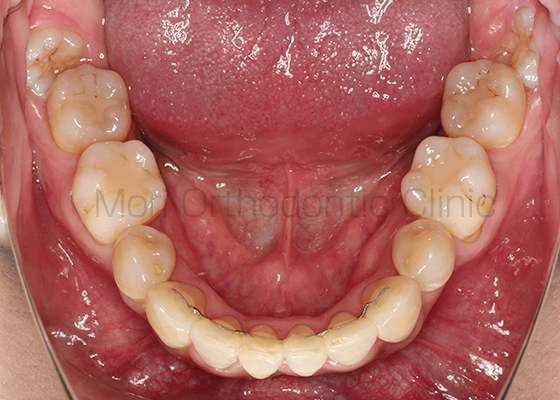

術前